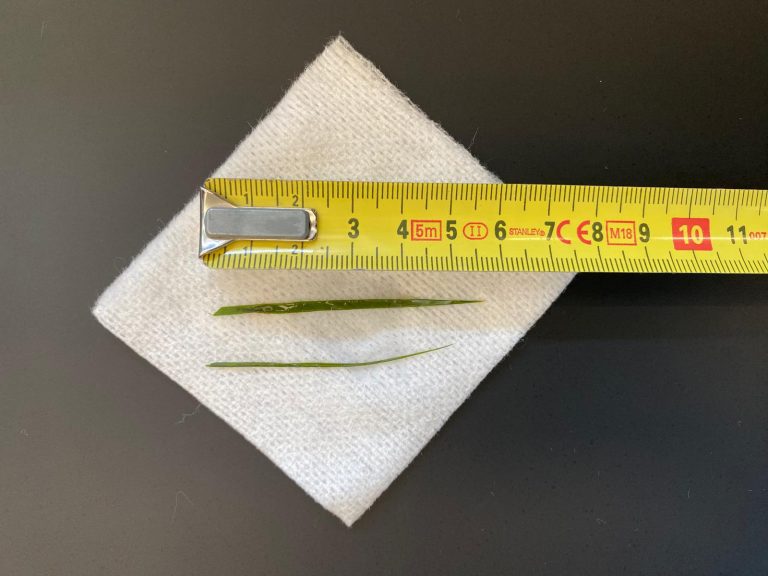

Hieronder ziet u een aantal foto’s van de operatie:

(bij de verwijderde testikels, ziet u links de normale testikel. Deze is ongeveer 3 cm breed, dit geeft een beeld van de grootte van de tumoreuze testikel).